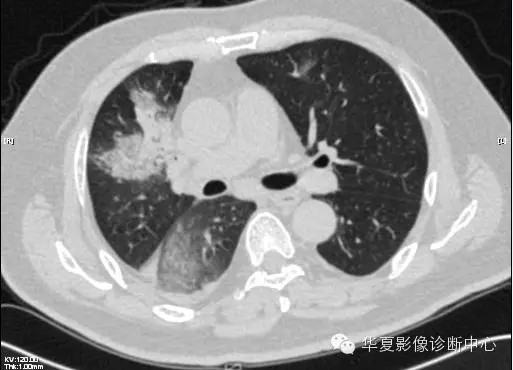

【病例学习】甲型H7N9禽流感一例

男性 63

发热咳嗽5天

2013-4-5拍片示右肺实变,收入院,追问病史,发病期间肌肉酸痛,头痛,无腹痛腹泻,无明显胸闷气急,无意识改变。有高血压病史,无其它病史。

2013-4-7CT进一步检查。

最终诊断:H7N9。